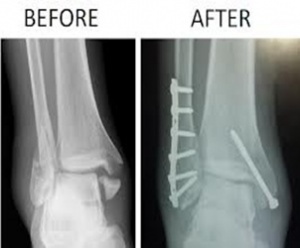

Fractured tibia & fibula at condylar region before & after surgery.